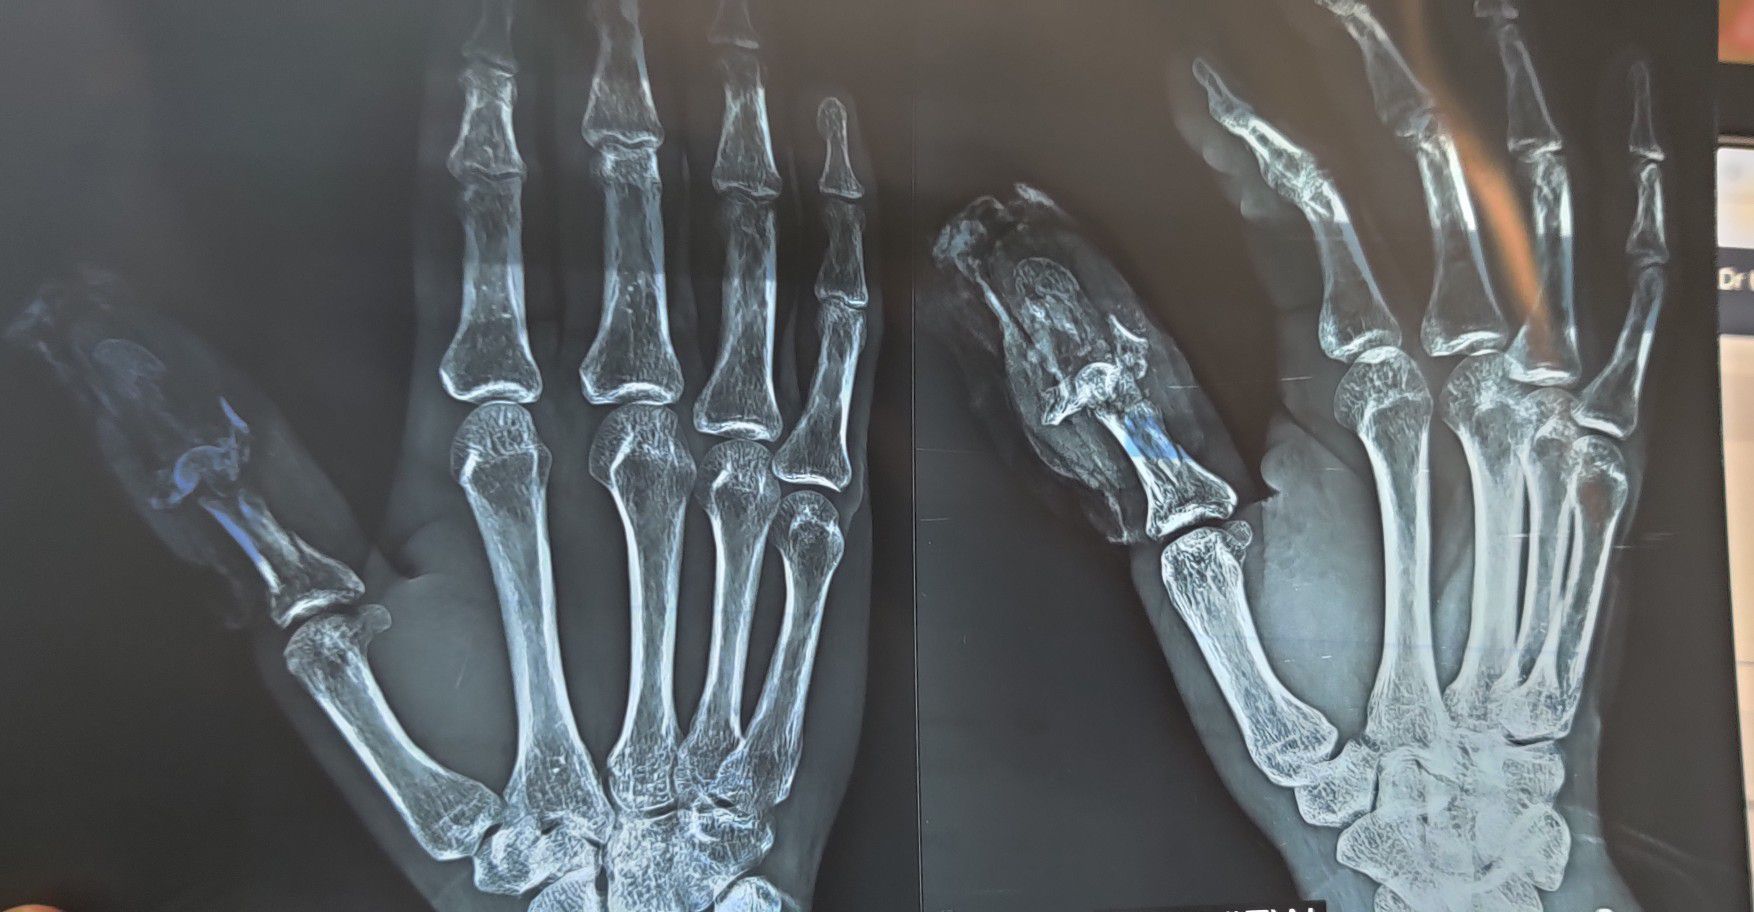

Traumatic Injury to Thumb

Trauma

Xray

Orthopaedics